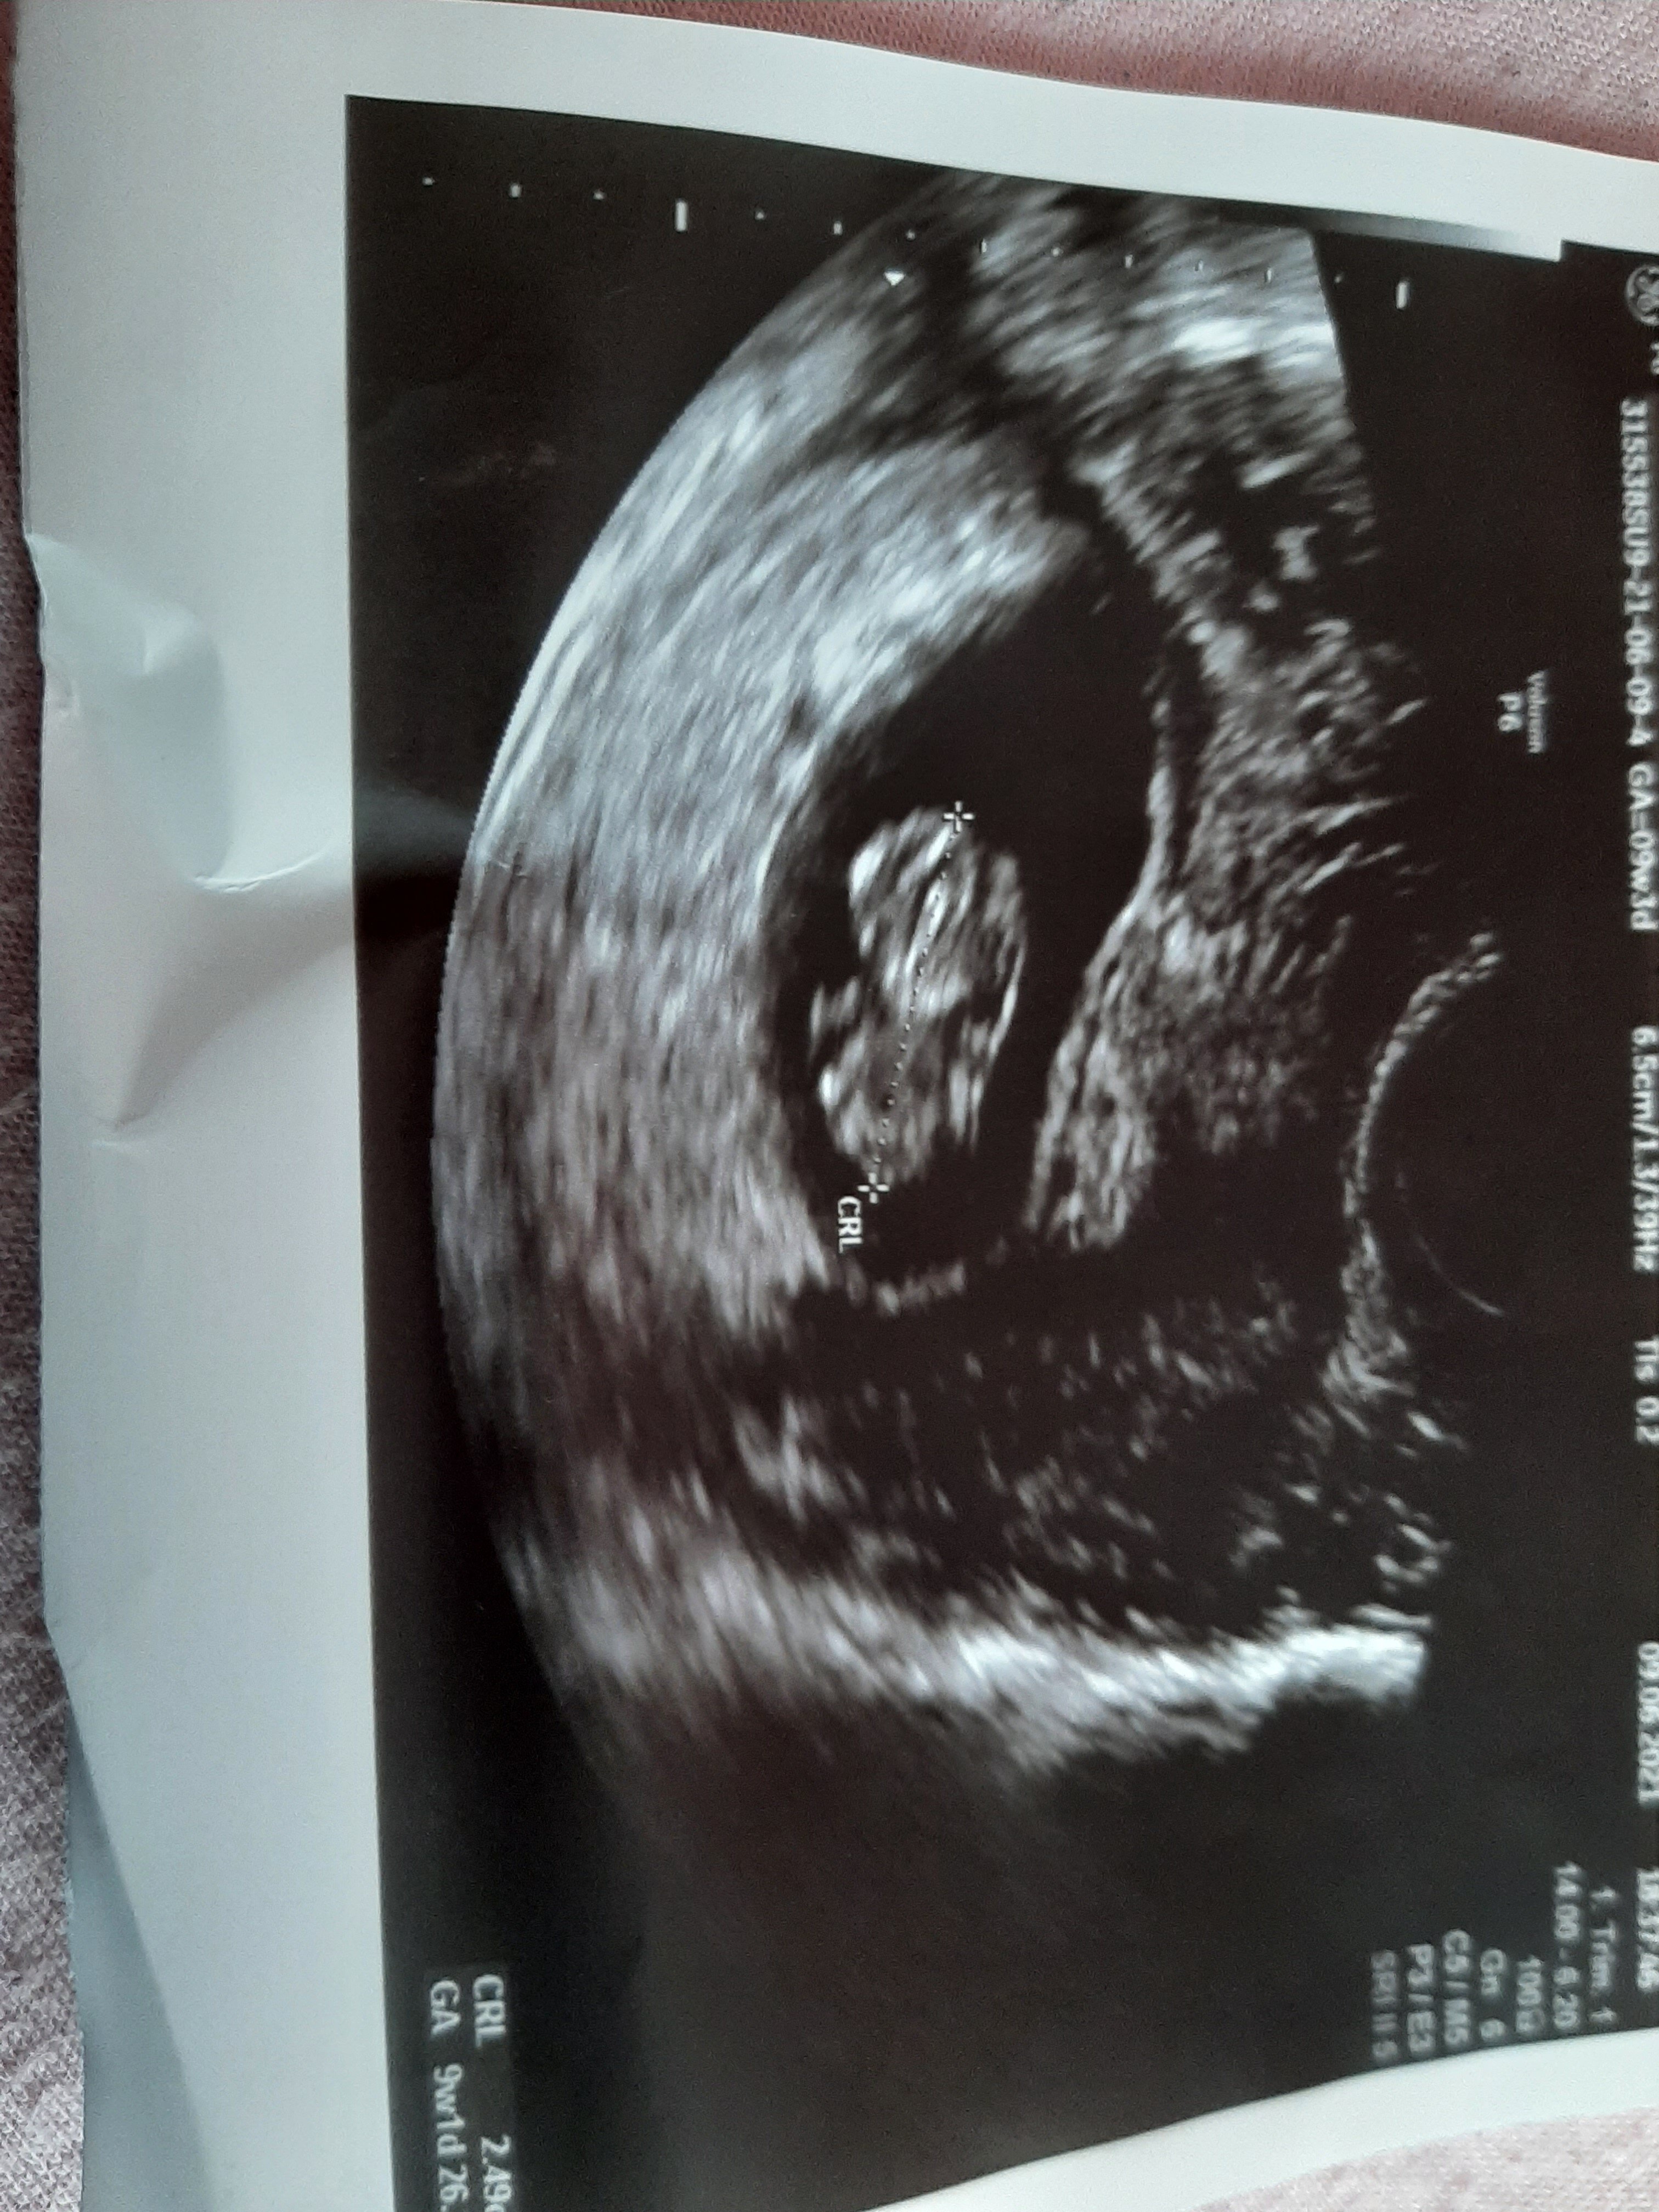

Wczoraj byłam na wizycie ale juz zabrakło mi dnia zeby Wam napisac. Wszystko w porzadku :) Gumiś jest i rośnie. Wg Om 9+3, wg usg 9+1. 2,6cm szczęscia. Serduszko ładnie bije. Prenatalne 28 czerwca.

Zalaczam zdjecie Gumisia, nie takie wyraźne jak u niektorych ale piekne :)

• 20210610_073416.jpg

20210610_073416.jpg

1,5 MB · Wyświetleń: 96